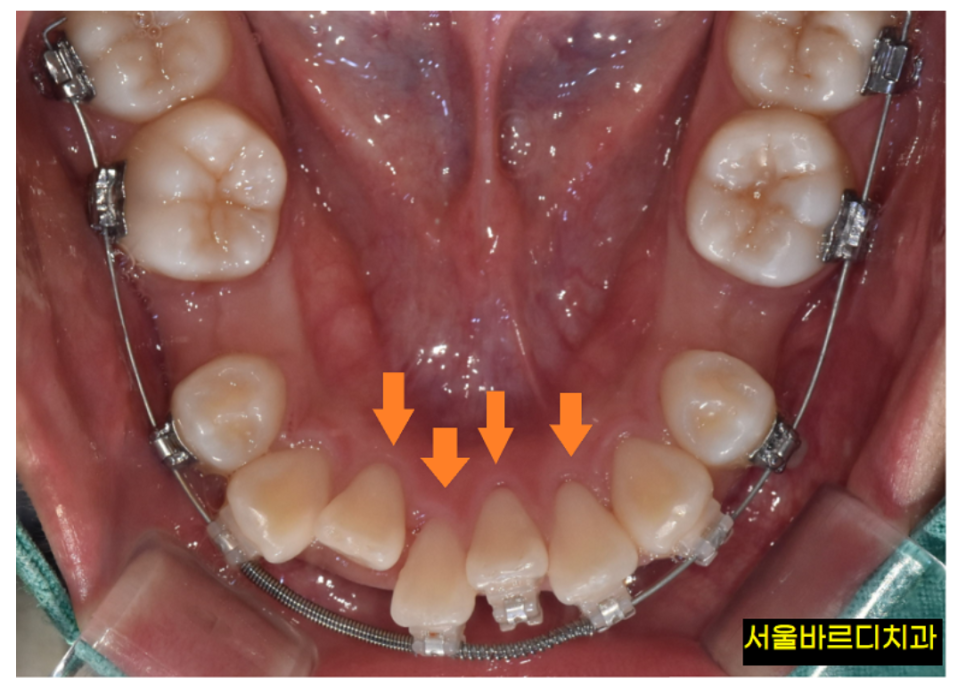

뼈가 녹아야 치아가 움직입니다

교정은 치아를 움직이는 것입니다.

그런데 치아는 뼈 속에 박혀있죠?

이 치아를 움직인다는 건,

뼈 안에 단단히 박혀있는 치아 뿌리를 이동시켜야하고

그 과정에서 뼈는 흡수되었다 다시 생성되는 과정을 반복해야 합니다.

치아 배열 상태가 삐뚤빼뚤 할수록